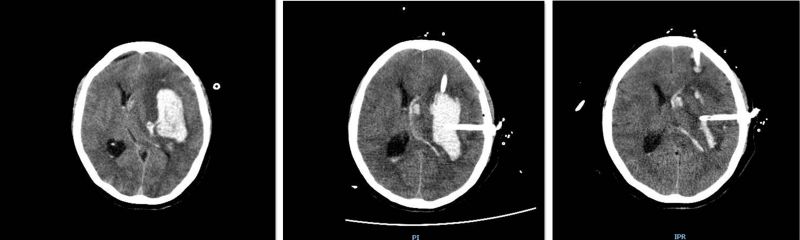

脑出血治疗的关键是尽早地清除血肿,急诊重症监护病房副主任、神经外科专家潘继明立即与患者家属谈话,征得家属同意后,在急诊重症监护病房床边给予头部备皮,半小时即完成血肿穿刺碎吸术。术后第二日,患者瞳孔回缩,复查CT显示血肿明显减少,继续给予冰毯控温、脑保护等综合治疗,术后第五日即转入普通病房,继续康复治疗。

软通道血肿穿刺碎吸术(术前) 软通道血肿穿刺碎吸术(术中) 软通道血肿穿刺碎吸术(术后)